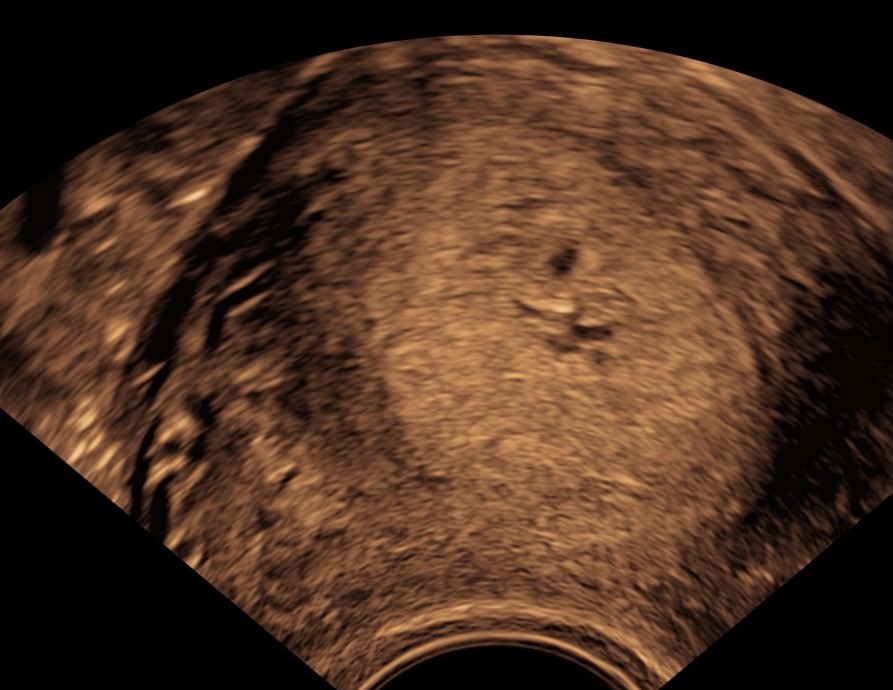

jeg fik en scanning i uge 4+5, hvor der var to større sorte prikker på, med en tydelig blommesæk i den ene. Min gynækolog sagde, at det var ret almindeligt at der var anlæg til muligvis to sække i den helt spæde fase, men at de fleste ikke udvikler sig eller indeholder noget (og man derfor ikke ved det, fordi de færreste bliver scannet så tidligt).

Da jeg blev scannet to uger efter var den mindste sorte prik (uden blommesæk) væk, men den anden voksede lige som den skulle